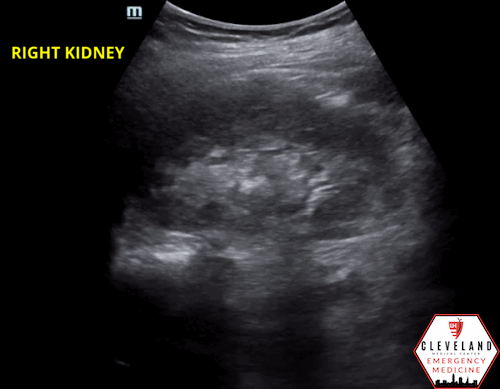

Renal POCUS was performed to evaluate for hydronephrosis and showed the following:

POCUS findings:

There is hydronephrosis of the left kidney. The right kidney is normal-appearing. Bladder views incidentally revealed a large complex, fluid-containing lesion in the pelvis (color doppler negative).